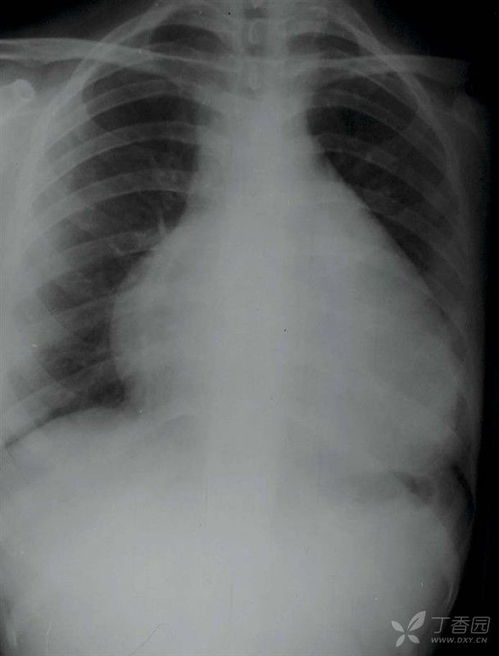

众所周知,吸烟是众多癌症的罪魁祸首。其中,肺癌无疑是最为引人瞩目的。对于那些长期沉浸在烟雾缭绕中的人,患肺癌的风险比那些远离烟草的人高出整整10到30倍。肺癌中的小细胞肺癌,更是与重度吸烟有着直接的联系,其恶性程度高且易于转移。

据统计,长期吸烟者的肺癌累积风险高达30%,这是一个多么惊人的数字!而那些选择终身不吸烟的人,其风险显然要低得多。事实上,大约90%的肺癌患者都有吸烟的暴露史,这包括主动吸烟和被动吸烟。更糟糕的是,每200名长期吸烟的人中,就有约36人可能会患上肺癌,而高达120人可能会死于与吸烟相关的疾病。在2020年,中国的肺癌病例占所有新发癌症的近五分之一,且其死亡率居高不下。